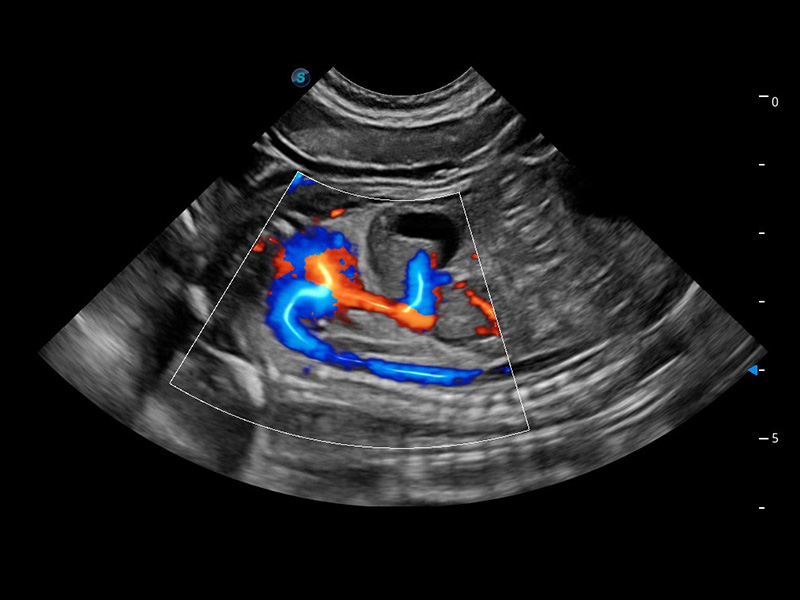

ProPet 60 作为一款高端台式动物超声设备,为动物医生的日常诊断提供了一系列贴合动物临床需求、解决临床实际问题的高级成像功能。凭借全系列高清探头,满足医生对腹部、心脏、生殖、浅表、肌骨等成像的所有需求,切实帮助您提升检查效率,提高诊断信心。

动物是人类最亲密的朋友和最值得信赖的伙伴。玖鼎集团也一直致力于探索动物专用的超声影像解决方案。 全新推出的ProPet系列,是玖鼎集团在动物超声影像智能化、专业化、精准化的一次跨越式革新。动物不能用言语来表述自己的不适,通过超声影像,ProPet系列搭建了动物医生与不同物种沟通的“桥梁”,为动物医生注入了“治愈之力”。